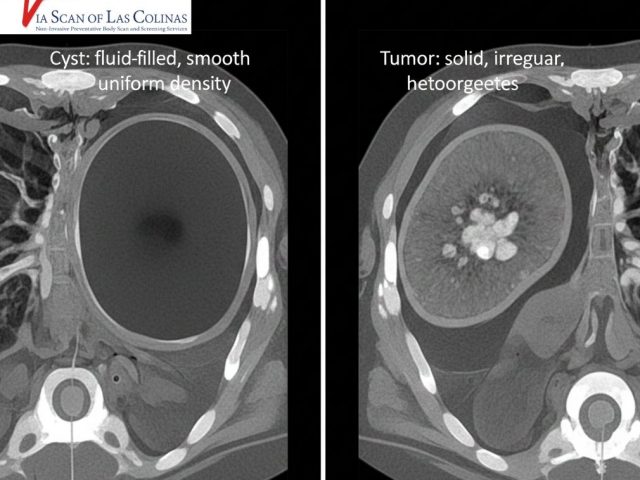

ViaScan is a provider of wellness body scans, heart scans, lung scans, virtual colonoscopy, and virtual angiograms has been serving patients and saving lives since June 2001. Owned and operated by John Duncan, Ph.D., ViaScan is known for being one of the best imaging facilities in North Texas. We have top-of-the-line scanners that are equipped with advanced technology. This high-speed technology allows for a 3-Dimensional Study of the internal organs, scanning much more anatomy than the typical conventional scan. These scans can include images of the heart, lungs, carotid arteries, and all of the abdominal organs and can be used to screen for abnormalities such as inflammation, blockages, or even cancer so as to alert patients to concerns before they become symptomatic since problems caught early are often modifiable, reversible and curable.

ViaScan of Las Colinas is a healthcare imaging company, founded by John Duncan, Ph.D. We provide a variety of non-invasive preventative body scans and screening services. Since June 2001, ViaScan has served patients and saved lives. Our services include wellness body scans, heart scans, lung scans, virtual colonoscopy, and angiograms scan. These non-invasive exams are designed to detect heart disease, lung cancer, colon cancer and other life-threatening diseases at an earlier, more treatable stage.

Our scan can see stages of heart disease and cancer in their infancy. Providing these early indicators to our patients allows him/her a head start and the possibility of reversing the clock on a potentially severe illness. ViaScan’s mission is to provide you with the most advanced technology, support, and education to empower you to improve your health. We are one of the first centres in the United States to offer preventive scanning and screening services and include a comprehensive evaluation.

ViaScan is one of the best imaging facilities in North Texas that uses a top of the line scanner with minimal radiation. This high-speed technology allows for a 3-Dimensional Study of the internal organs scanning more than conventional scans.